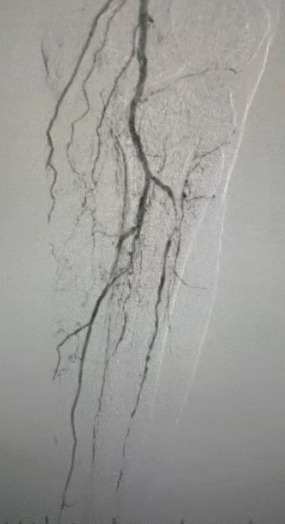

Surgical Outcome

Post-procedure, arterial stenosis improved significantly, blood flow increased, and skin temperature rose. No postoperative complications occurred. Both the patient and surgical team were highly satisfied with the results.